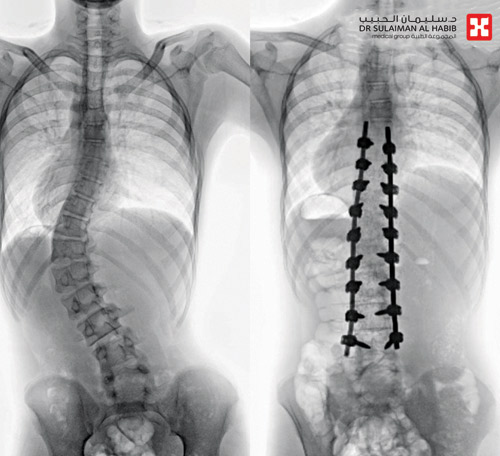

وقال د. خليفة إن المريض راجع المستشفى وهو يشتكي من انحناء جانبي للعمود الفقري منذ سنوات، ثم بدأ يعاني مؤخراً من صعوبة في ممارسة أنشطته اليومية، ما أدى إلى تغيير نمط حياته وتقييد حركته، وفور وصوله إلى المستشفى أجريت له التحاليل والفحوصات الطبية الدقيقة اللازمة، التي بينت إصابته بحالة انحراف «جنف» بدرجة «60»، في الفقرات القطنية ودرس الفريق الطبي الحالة على ضوء نتائج الفحوصات والتحاليل، وخلص إلى ضرورة التدخل الجراحي لعلاج العيوب، والحد من المضاعفات، وبعد اتخاذ كافة التدابير الطبية لمثل هذه الحالات المعقدة أجريت العملية للمريض وتم خلالها تقويم العمود الفقري بعدد «18» من البراغي والقضبان المعدنية والطعوم العظمية الصناعية وتثبيت ودمج الفقرات، وبعدها نقل المريض إلى جناح التنويم وبدأت حالته في التحسن بشكل متسارع حيث استطاع المشي بتوازن بعد أقل من «24» ساعة من العملية بإشراف ومتابعة من فريق العلاج الطبيعي، واستعاد المريض قدرته على الاستلقاء والنوم على ظهره، فضلاً عن استعادته للقوام والمظهر الطبيعي بعد تعديل وضعية الحوض والكتف، كما أن طوله مع النجاح الكبير للتعديل زاد بحدود «3» سم، وخرج من المستشفى وهو بصحة جيدة، ويتوقع أن يستعيد كامل عافيته سريعاً، بعد استكمال البرنامج العلاجي المصمم له.